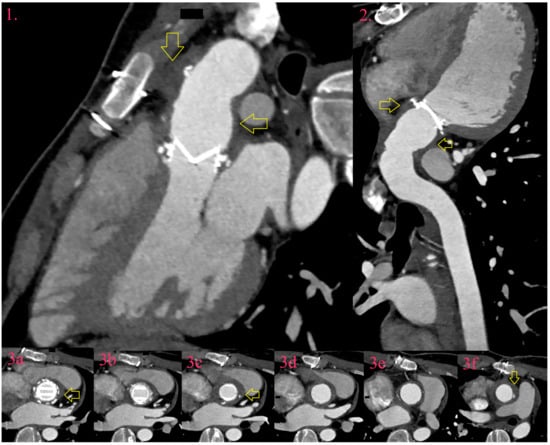

7.4. Leak